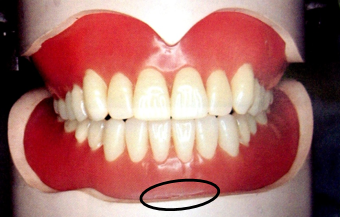

临床上,根据无牙颌每个解剖部位的不同特点,全口义齿制作时都要做相应的特殊处理,这与全口义齿的固位、稳定、美观、功能等都息息相关。

无牙颌的分区:

①主承托区:垂直于颌力受力方向的区域。包括牙槽嵴顶、腭部穹隆区、颊棚区等,该区不易出现骨吸收,能承担咀嚼压力。

②副承托区:与牙合力受力方向成角度的区域。包括上下颌牙槽嵴顶的唇、颊和舌腭侧(不包括硬区),与颊舌的界限在粘膜和口腔前庭黏膜反折线,支持能力较差,不能承受较大压力,只协助主承托区承受咀嚼压力。

③边缘封闭区:义齿边缘接触的软组织部分,如黏膜皱襞、系带附着部、上颌后堤区和下颌磨牙后垫。

此区有大量疏松结缔组织,与义齿边缘紧密贴合,防止空气进入基托与组织之间,产生良好的边缘封闭作用,从而形成负压和吸附力保证义齿固位。

④缓冲区:无牙颌上的颧突、上颌结节的颊侧、切牙乳突、下颌隆突、颌舌骨嵴,牙槽嵴上的骨尖、骨棱等部位。这些部位粘膜较薄,基托相应部位应磨除少许做缓冲处理。

⑤后堤区: 腭小凹后方,轻压颤动线以获得良好的封闭。